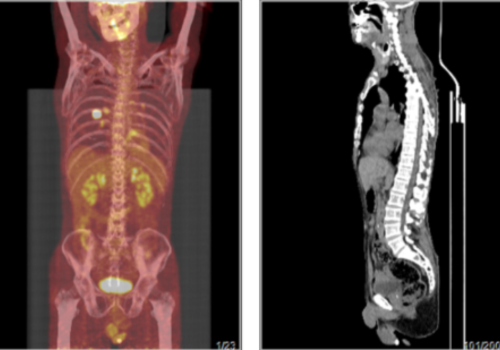

简要病史:2020-1-17我院PETCT示回盲部肿瘤术后,木区片状FDG代谢增高,考虑术后改变,建议结合临床。双侧颈部小淋巴结FDG代谢轻度增高,考虑炎症,建议随访。前次检查后患者化疗6次,末次化疗时间2020-5,现患者偶有咳嗽,余无特殊不适主诉。意识:清楚;空腹血糖:5.0 mmol/L;诊断结果:1.淋巴瘤治疗后;所见骨髓FDG代谢弥漫性增高,考虑骨髓反应性增生可能大,建议必要时结合骨髓穿刺相关检查以除外肿瘤骨髓浸润可能。2.回盲部肠道FDG代谢轻度增高,考虑炎性或治疗后改变可能大,建议随访;余所见全身(包括脑)PET显像未见FDG代谢明显异常增高灶。3.副鼻窦炎。